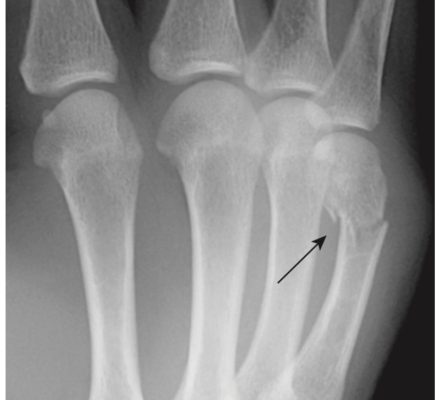

- Gãy xương của võ sĩ quyền anh (Boxer’s fracture): gãy cổ của xương bàn đốt ngón tay thứ 5 (ngón út) với di lệch gập góc về lòng bàn tay của đầu xa. Đôi khi cũng bị thêm xương bàn đốt ngón thứ 4. Gãy xương này thường do đấm tay vào người hoặc vào tường (Hình 13). Dù tên gọi võ sĩ quyền anh, những võ sĩ chuyên nghiệp thường không bị loại gãy này (lực đấm đúng thường tác động lên các xương đốt bàn ngón 2 và ngón 3 và xương quay).